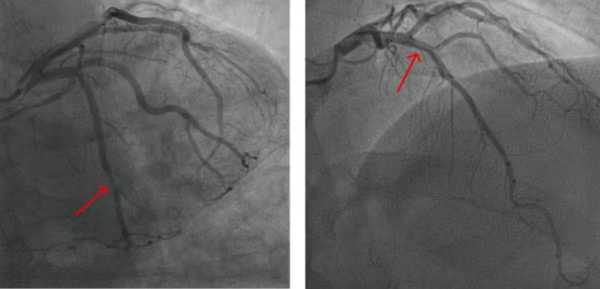

Жінки частіше, ніж чоловіки, мають серцево-судинні захворювання, які проявляються у вигляді множинних звужених артерій, які не повністю «закупорені», що призводить до болю в грудях, оскільки кровотік не може достатньо прискоритися, щоб задовольнити підвищені потреби в кисні під час фізичних вправ, подібно до низькопоточного душу. Коли біль у грудях проявляється таким чином, лікарі називають цей стан ішемією та відсутністю обструктивних коронарних артерій. Для порівняння, у чоловіків частіше виникає «закупорка» артерії в концентрованій ділянці, яку можна відкрити за допомогою стента або операції шунтування серця. Варіанти лікування множинних звужених артерій відстають від варіантів лікування типових «закупорених» артерій, що ставить жінок у невигідне становище.

Жінки мають вищий ризик смерті від серцевих захворювань. Ось чому. | INFBusiness

Кровоносні судини не обов'язково повинні бути закупорені нальотом, щоб спричинити серцеві захворювання.